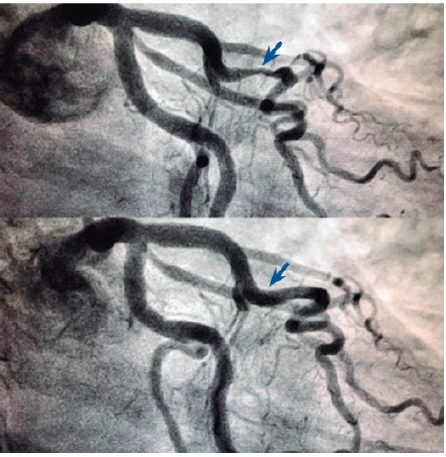

Paciente está em investigação de dor torácica atípica com teste ergométrico apresentando alterações sugestivas de isquemia miocárdica, próximo ao pico do esforço, com melhora nos primeiros segundos da recuperação. O médico assistente optou por solicitar a cinecoronariografia visualizada abaixo (durante a sístole, figura superior e na diástole, inferior).

Nesse caso, o diagnóstico é